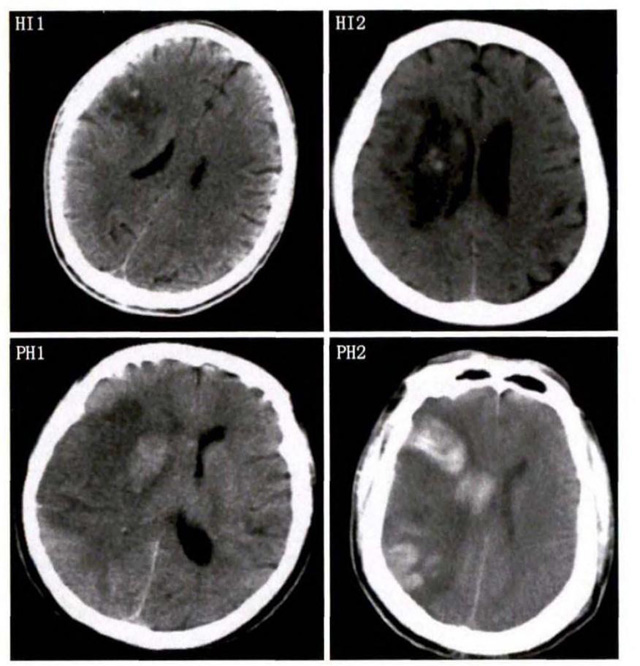

中、老年病患,有动脉粥样硬化及高血压病等脑卒中的危险因素,发病结合神经系统症状和体征,应当考虑急性脑梗死的可能。再经脑CT/MRI发现梗死灶,或排除脑出血、炎症性疾病等,诊断即可确定。脑梗死有时颇似小量脑出血的临床表现。脑栓塞在任何年龄都可以有发病的风险,可以在几秒到几分钟达到顶峰?;嵊衅辈荒芩祷暗染植可窬δ芩鸹?。栓子来源很种,可能是冠心病、心肌梗塞、心内膜炎等。合并心房纤颤,结合其他脏器官的支持诊断,CT跟磁共振都可以检查确定栓塞位置数量还有是不是有伴发出血等问题??梢园镏锒?。

中老年有高血压糖尿病发病病史,起病神经功能缺损症状,临床表现为腔隙综合征,即可初步诊断本病。如果CT或磁共振证实有与神经功能缺失一致的脑部腔隙病灶, 符合大脑半球或脑干深部的小穿通动脉病变,即可明确诊断。少数患者隐匿起病,无明显临床症状,在影像学检查时发现。